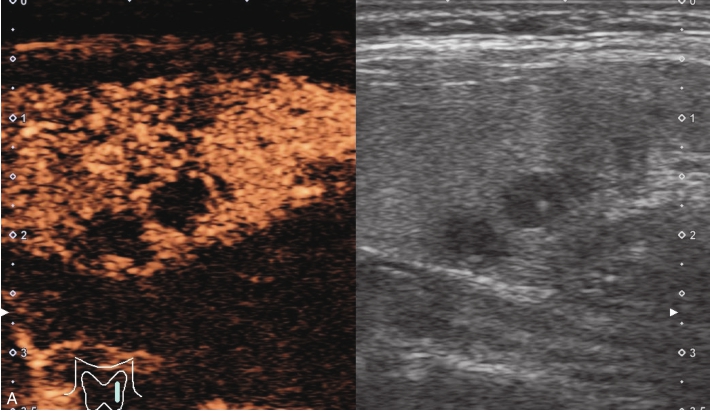

甲状腺形态基本正常,甲状腺实质回声稍增粗,分布尚均匀,甲状腺包膜尚光滑。甲状腺两叶内见多发结节,较大者位于左叶上极,呈类椭圆形,边界清楚,形态规则,纵横比<1,内部回声均匀,未见钙化,后方回声稍增强。CDFI显示左叶较大结节边缘可见丰富的条状血流信号,内部可见条状、点状血流信号,见图1-3-7。

图1-3-7 结节性甲状腺肿常规超声表现

A.常规超声图像;B.CDFI超声图像

甲状腺左叶上极较大结节增强早期呈稍高增强,自结节外周向中央灌注,增强晚期呈等增强,结节内部可见不均匀低增强区,见图1-3-8、ER1-3-4。

图1-3-8 结节性甲状腺肿超声造影图像